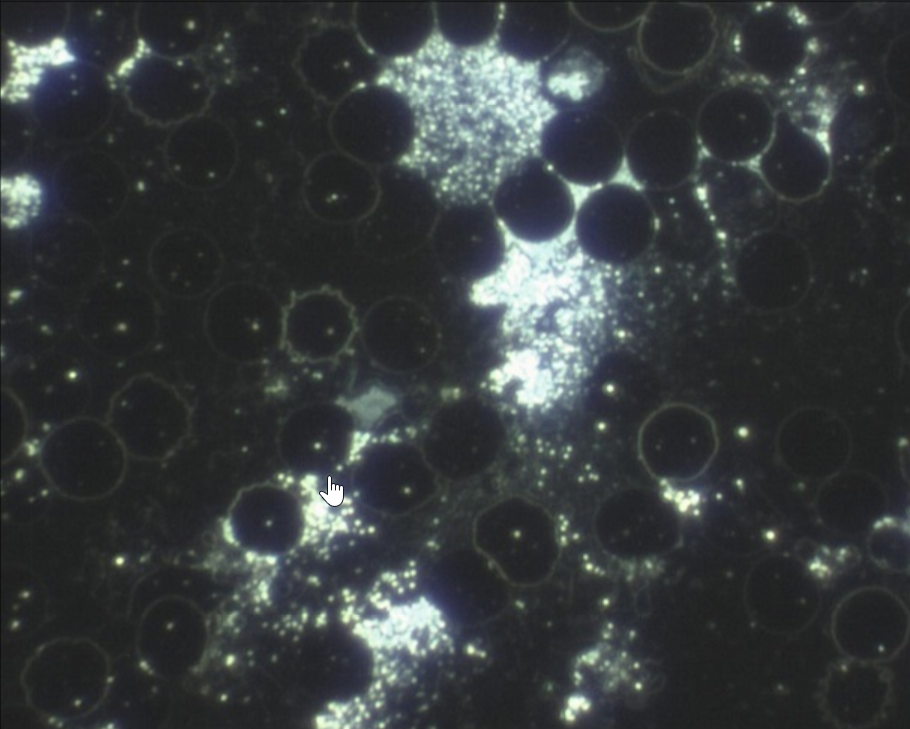

Manch Einer fragt sich warum werde ich krank und der Andere nicht. Mikroorganismen können sich unter bestimmten Verhältnissen einfach besser entwickeln. Ein gestörtes Körpermilieu ist der beste Nährboden für Erkrankungen. Genau hier setzt diese Untersuchungs- und Behandlungsmethode nach Prof. Dr. Enderlein an. Bei diesem Diagnoseverfahren wird mit Hilfe des Dunkelfeld-Mikroskops ein Tropfen Blut untersucht. Aufgrund der speziellen physikalischen Vorraussetzungen des Dunkelfeld-Mikroskops können Phänomene im Blut erkannt werden und so Rückschlüsse auf Veränderungen im Körpermilieu gezogen werden. Es wird die Anzahl, Form und Beweglichkeit der Weißen und roten Blutkörperchen untersucht, die Lage der Blutblättchen beurteilt und Erscheinungsformen im Plasma bestimmt.

Beispiele: